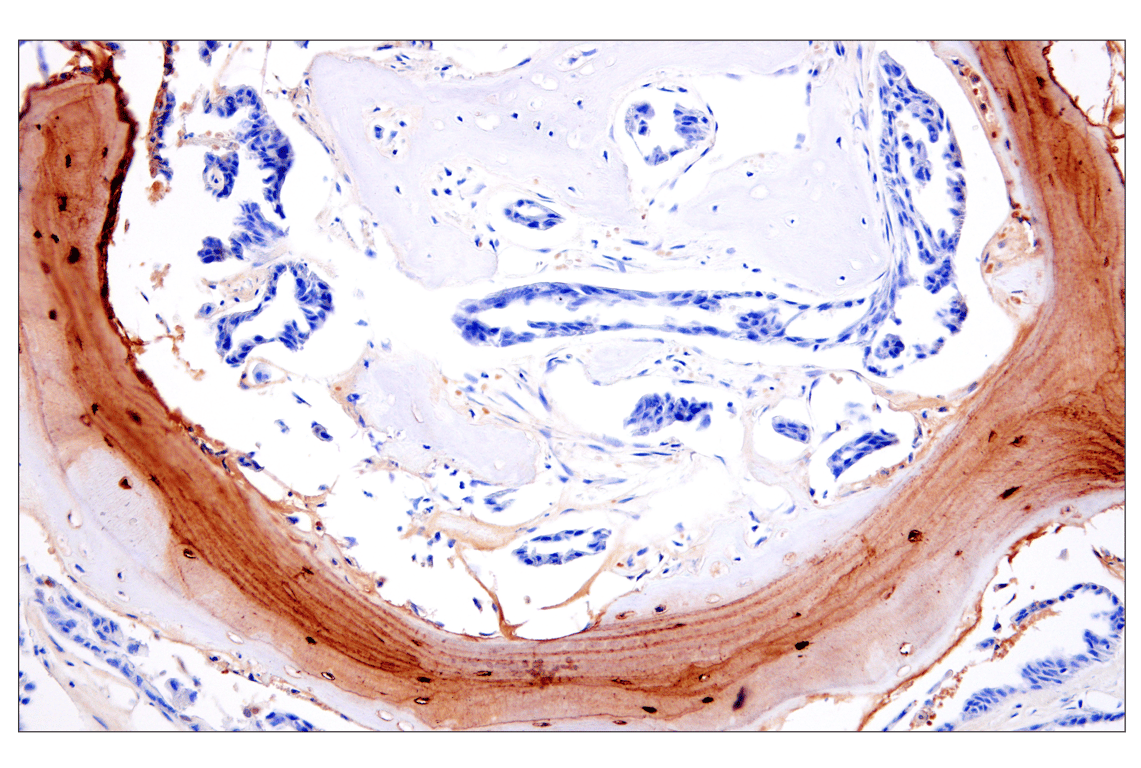

Immunohistochemical analysis of paraffin-embedded human osteosarcoma using Osteocalcin (E8B9X) Rabbit mAb.

Immunohistochemistry Image 1: Osteocalcin (E8B9X) Rabbit Monoclonal Antibody

Immunohistochemistry Image 2: Osteocalcin (E8B9X) Rabbit Monoclonal Antibody